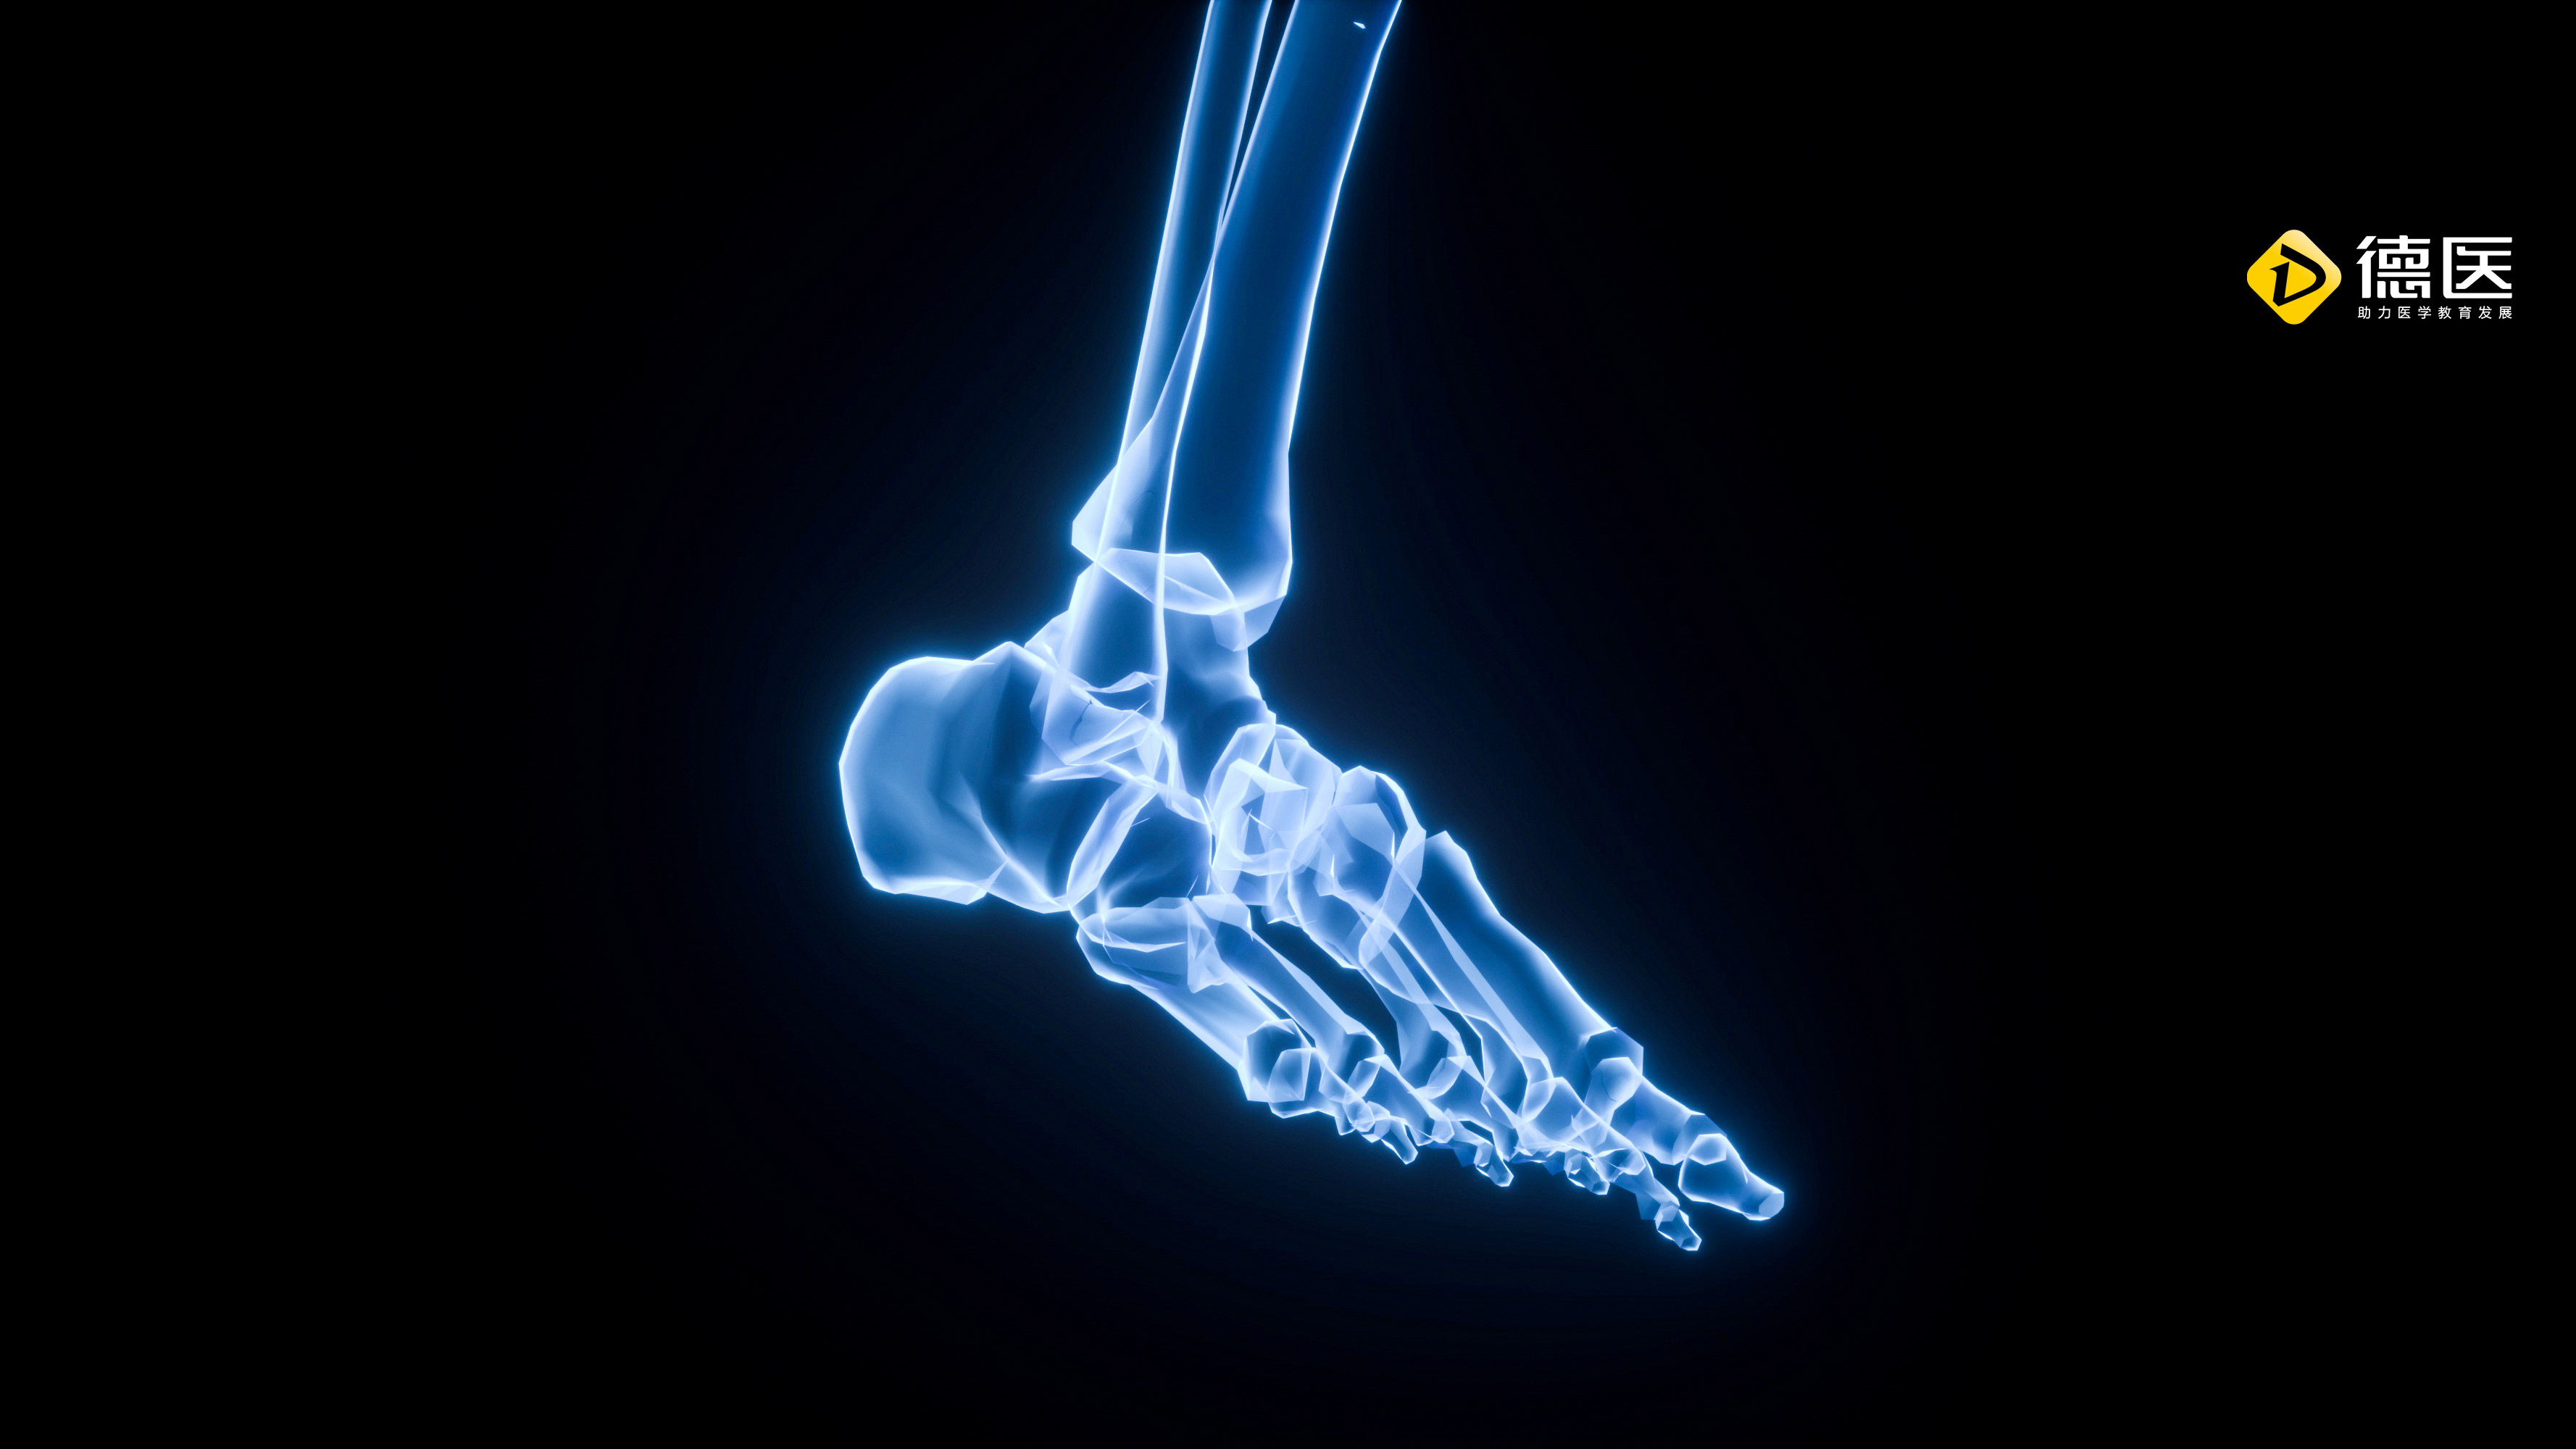

高清图普:足踝部解剖及影像学,基础必备!